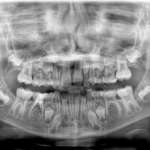

Valutazione della prevalenza di agenesie dentali tramite ortopantomografie in un campione di residenti in... Free

L’agenesia è una delle più frequenti anomalie dentali. Poiché in letteratura si riporta un ampio range di prevalenza (da 1.6% a 36.5%), l’obiettivo del presente studio è definire la frequenza di agenesia dentale in un campione di soggetti residenti in Piemonte e Lombardia. Diagnosticare la mancanza di un elemento dentale precocemente è importante per pianificare il corretto piano di trattamento.